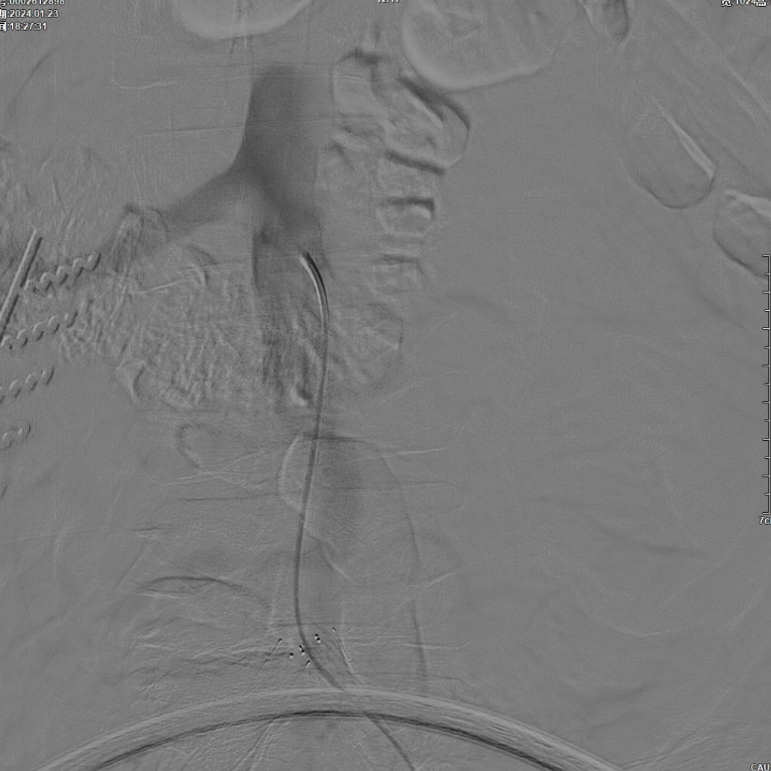

CERAB技术的关键点一:经双侧股总动脉植入2枚VBX球囊扩张式覆膜支架(8L×79mm),与腹主动脉覆膜支架腔内平行放置,且两枚支架端平齐对接。

CERAB技术关键点二:先用14mm×40mm球囊分别扩张双侧髂肢的腹主动脉段。

再用8mm球囊对双侧髂支腹主动脉段行对吻扩张,以确保双侧髂支与腹主动脉覆膜支架腔内获得良好的贴壁形态,最大程度减少空腔,降低远期再狭窄发生率。